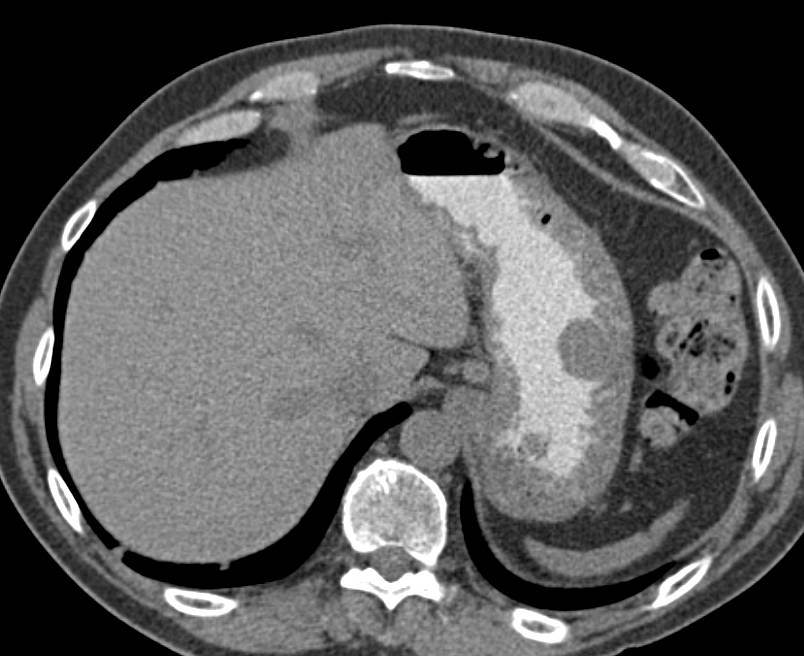

Gastric GIST Tumor